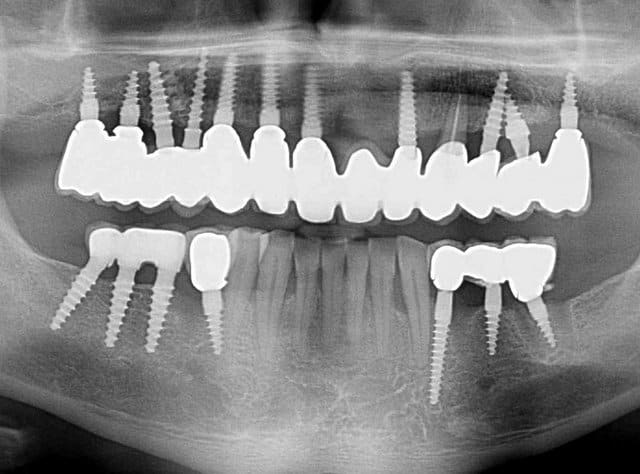

Pour ceux que ca interessent, et parce qu on a m a demandé des cas supplémentaires dans le sujet 23 implants rehabilitation totale, voici un autre cas d implantation immédiate avec la technique minimalement invasive et condensation grace aux forets.

Le patient a reçu un traitement il y a dix ans dans le maxillaire et dans le 4eme quadrant.Comme on peut le voir j´ai du extraire quelques dents au maxillaire: 35 37 et 45.

Le septum de la 37 a été foré avec un foret conique 3 faces.

J ai planté à 60 Ncm sans fracturer le septum.Juste après l opération , les prep caps en zircon ont été cémenté.La restauration définitive 34 jusqu` à 37 été fixé 2 semaines après l implantation avec implantlink (detax). Après un an, le bridge a été retiré facilement pour voir l´état de la gencive et faire une radio de contrôle.On la re ossifiction est satisfaisante et que la gencive "aime" le zircon.

Le bridge a ensuite été recémenté sans correction nécessaire du bridge.

non, c'est pas de l'occlusion dont je parle...mais de l'adaptation prothèse/pilier implantaire (il y a un espace entre l'implant et l'armature métallique de la prothèse au niveau des molaires...mais pas que...) source de rétention de plaque dentaire et donc risque potentiel de périimplantite à ce niveau...

ah je comprends mieux!!! :-),les "espaces" que tu vois ce sont des prep caps en zircon avec prothèse zircone il n y donc pas d accumuation de plaques sinon tu aurai raison ! (bonne remarque). La couronne ne touche pas" l assiette" (en allemand on parle d assiette...)du prep cap ...